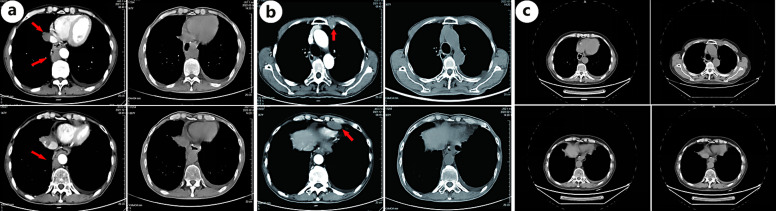

Case presentation: We report a male patient with SCCE. Despite aggressive management including surgery and salvage therapies, the patient experienced multiple recurrences within the first 2 years postoperatively. However, through vigilant surveillance facilitating early recurrence detection and prompt intervention - notably stereotactic body radiotherapy (SBRT) combined with immunotherapy - a potential abscopal effect was observed. Remarkably, the patient achieved a durable complete remission and long-term survival, remaining alive with minimal complications at 61 months post-diagnosis and continuing follow-up.